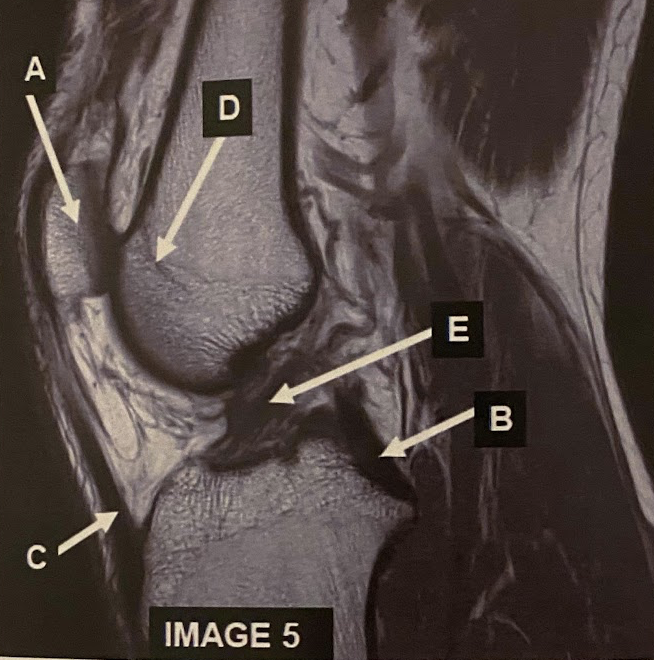

The sagittal scan, demonstrates typical hyper intense tendril-like projections in the corpus callous characteristically seen in patients with what disease?

C) Multiple Sclerosis

What anatomy is letter A pointing to?

Pons

What anatomy is letter B pointing to?

Corpus Callosum

What anatomy is letter C pointing to?

Medulla Oblongata

What anatomy is letter D pointing to?

Fourth ventricle

What anatomy is letter E pointing to?

Aqueduct of Sylvius

What anatomy is letter F pointing to?

Genu of the corpus callous

What anatomy is letter G pointing to?

Pituitary

What anatomy is letter H pointing to?

Mammillary Bodies

What anatomy is letter I pointing to?

Quadrigeminal plate